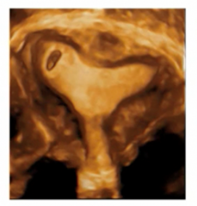

Intramural uterine ectopic pregnancy

Auch Schwangerschaften, die sich in Narben nach Myomektomie implantieren, sollten als intramural bezeichnet werden, sobald sie oberhalb des inneren MM gelegen sind.

Typischerweise in einer myometranen Narbe nach Operation, nach Ruptur oder innerhalb eines Adenomyose-Fokus

Partial intramural uterine ectopic pregnancy:

- First-Line Therapie: transzervikale Curettage unter sonographischer Sicht

Complete intramural uterine ectopic pregnancy:

- nicht zugänglich für transzervikale Curettage, Management somit medikamentös mittels MTX i.m. Einmaldosis oder Multi-Dose Schema